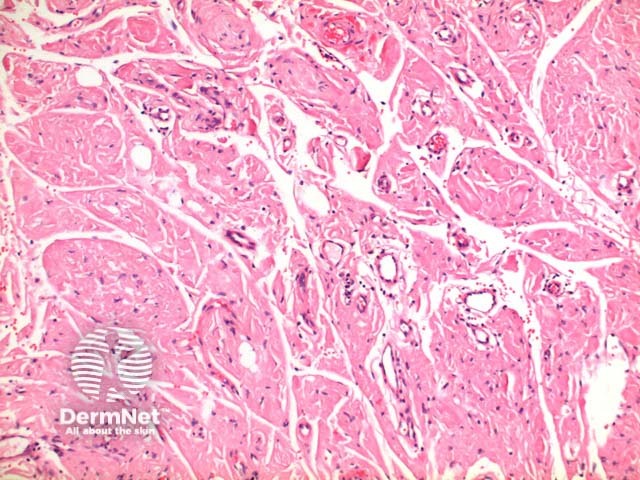

The scanning power view reveals a tumoral deposit within the dermis (figure 6). This may extend into the subcutaneous tissue (figures 7, 8, 9). Prominent clefting can be seen making superficial cases difficult to differentiate from colloid milium and paracolloid. The presence of numerous plasma cells in the accompanying inflammatory infiltrate, commonly with scattered Russell bodies, is helpful (figure 10).

Figure 8

Figure 9

Colloid milium and paracolloid: colloid milia are typified by superficial deposits of acellular amorphous material with prominent clefting. Paracolloid (colloid degeneration) may extend more deeply, with more subtle clefting, and has a more basophilic colour. Both entities are typically congo red negative while keratin antibody positive.